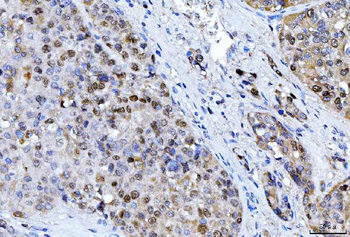

![Anti-FEN1 [SAIC-21C-4]](/images//pub/media/catalog/product/NewWebsite/35/orb1089994_1.png)

![Anti-FEN1 [SAIC-21C-4]](/images/pub/media/catalog/product/NewWebsite/35/orb1089994_2.png)

![Anti-FEN1 [SAIC-21C-4]](/images/pub/media/catalog/product/NewWebsite/35/orb1089994_3.png)